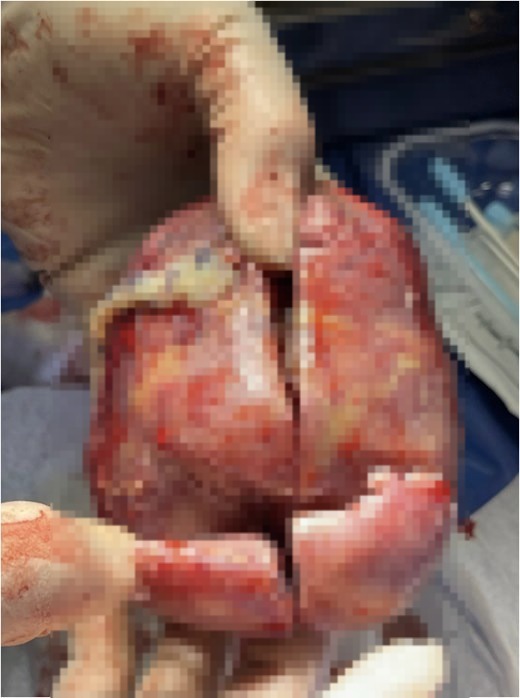

A team of surgeons at the Mansoura University Paediatric Unit performed a laparotomy (surgical incision into the abdomen) and discovered the mass located near the baby’s liver.

Upon removal, doctors were astonished to find that the mass contained fat, malformed tissue, two limbs, an umbilical cord, and even partially developed skin and intestines — resembling a partially formed twin.